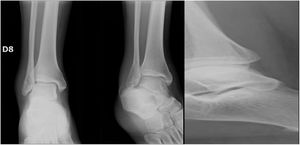

Materiales y MétodosSe realizó un ensayo auto-controlado, aleatorizado, doble ciego, multicéntrico, mediante la aplicación de encuestas en tres países a ortopedistas generales, subespecialistas en cirugía de pie y tobillo y residentes de ortopedia y traumatología. Se estableció el criterio de aleatorización simple mediante la presencia de los encuestados en los simposios de pie y tobillo en la ciudad de Guayaquil en el marco del congreso Ecuatoriano de Ortopedia y Traumatología, En la ciudad de Cali en el marco del curso nacional del Pie y Tobillo de la sociedad Colombiana de Cirugía Ortopédica y Traumatología y en la ciudad de Cancún en el marco del Congreso mexicano de Ortopedia y Traumatología de la FEMECOT, estableciéndose como criterio de inclusión estar en disposición de evaluar los casos clínicos y realizar la encuesta independientemente de su grado de entrenamiento o años de experiencia. Se entregaron cuatro casos de fracturas de tobillo Webber B de características quirúrgicas por sus mediciones radiológicas con desenlaces conocidos por los autores Senior (Eduardo Reina, Juan Manuel Herrera, Carlos Ramirez, Bosco Mendoza y Victor Toledo) como se observa en la figura 1.

En el caso 3 se estableció como criterio quirúrgico 1mm de discrepancia de la línea de shenton y una apertura de el espacio claro medial de 6mm, además de una malrotacion del peroné y discrepancia de el ángulo talocrural, como se observo en las figuras 6 y 7. figura 8, figura 9

En el caso 4 se estableció el criterio quirúrgico la diferencia de 9 grados en el ángulo talocrural con la radiografia comparativa y el espacio claro medial aumentado 1mm.